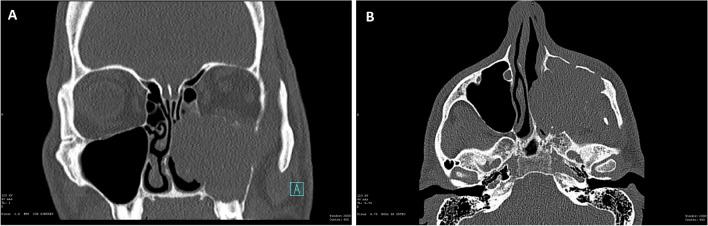

SMARCB1-deficient sinonasal adenocarcinoma is a rare variant of SWI/SNF-deficient malignancies with SMARCB1 loss and adenocarcinoma features. More than 200 high-grade epithelial sinonasal malignancies were retrieved. A total of 14 cases exhibited complete SMARCB1 (INI1) loss and glandular differentiation. SMARCA2 and SMARCA4 were normal, except for one case with a loss of SMARCA2. Next-generation sequencing (NGS) and/or fluorescence in situ hybridization (FISH) revealed an alteration in the SMARCB1 gene in 9/13 cases, while 2/13 were negative. Two tumors harbored SMARCB1 mutations in c.157C > T p.(Arg53Ter) and c.842G > A p.(Trp281Ter). One harbored ARID1B mutations in c.1469G > A p.(Trp490Ter) and MGA c.3724C > T p.(Arg1242Ter). Seven tumors had a SMARCB1 deletion. One carried an ESR1 mutation in c.644-2A > T, and another carried a POLE mutation in c.352_374del p.(Ser118GlyfsTer78). One case had a PAX3 mutation in c.44del p.(Gly15AlafsTer95). Histomorphology of SMARCB1-deficient adenocarcinoma was oncocytoid/rhabdoid and glandular, solid, or trabecular in 9/14 cases. Two had basaloid/blue cytoplasm and one showed focal signet ring cells. Yolk sac tumor-like differentiation with Schiller-Duval-like bodies was seen in 6/14 cases, with 2 cases showing exclusively reticular-microcystic yolk sac pattern. Follow-up of a maximum of 26 months (median 10 months) was available for 8/14 patients. Distant metastasis to the lung, liver, mediastinum, bone, and/or retroperitoneum was seen in 4/8 cases. Locoregional failure was seen in 75% of patients, with 6/8 local recurrences and 3 cervical lymph node metastases. At the last follow-up, 5 of 8 (62%) patients had died of their disease 2 to 20 months after diagnosis (median 8.2 months), and 3 were alive with the disease. The original diagnosis was usually high-grade non-intestinal-type adenocarcinoma or high-grade myoepithelial carcinoma. A correct diagnosis of these aggressive tumors could lead to improved targeted therapies with potentially better overall disease-specific survival.